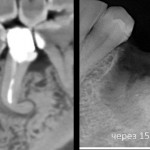

Через 3 месяца:

отличный результат остеопластики:

можно ставить импланты пятого и шестого зубов: